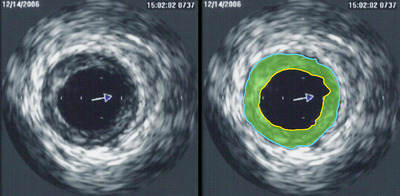

Intravascular ultrasound image of a coronary artery (left), with color-coding on the right, delineating the lumen (yellow), external elastic membrane (blue) and the atherosclerotic plaque burden (green). The percentage stenosis is defined as the area of the lumen (yellow) divided by the area of the external elastic membrane (blue) times 100. As the plaque burden increases, the lumen size will decrease and the degree of stenosis will increase.